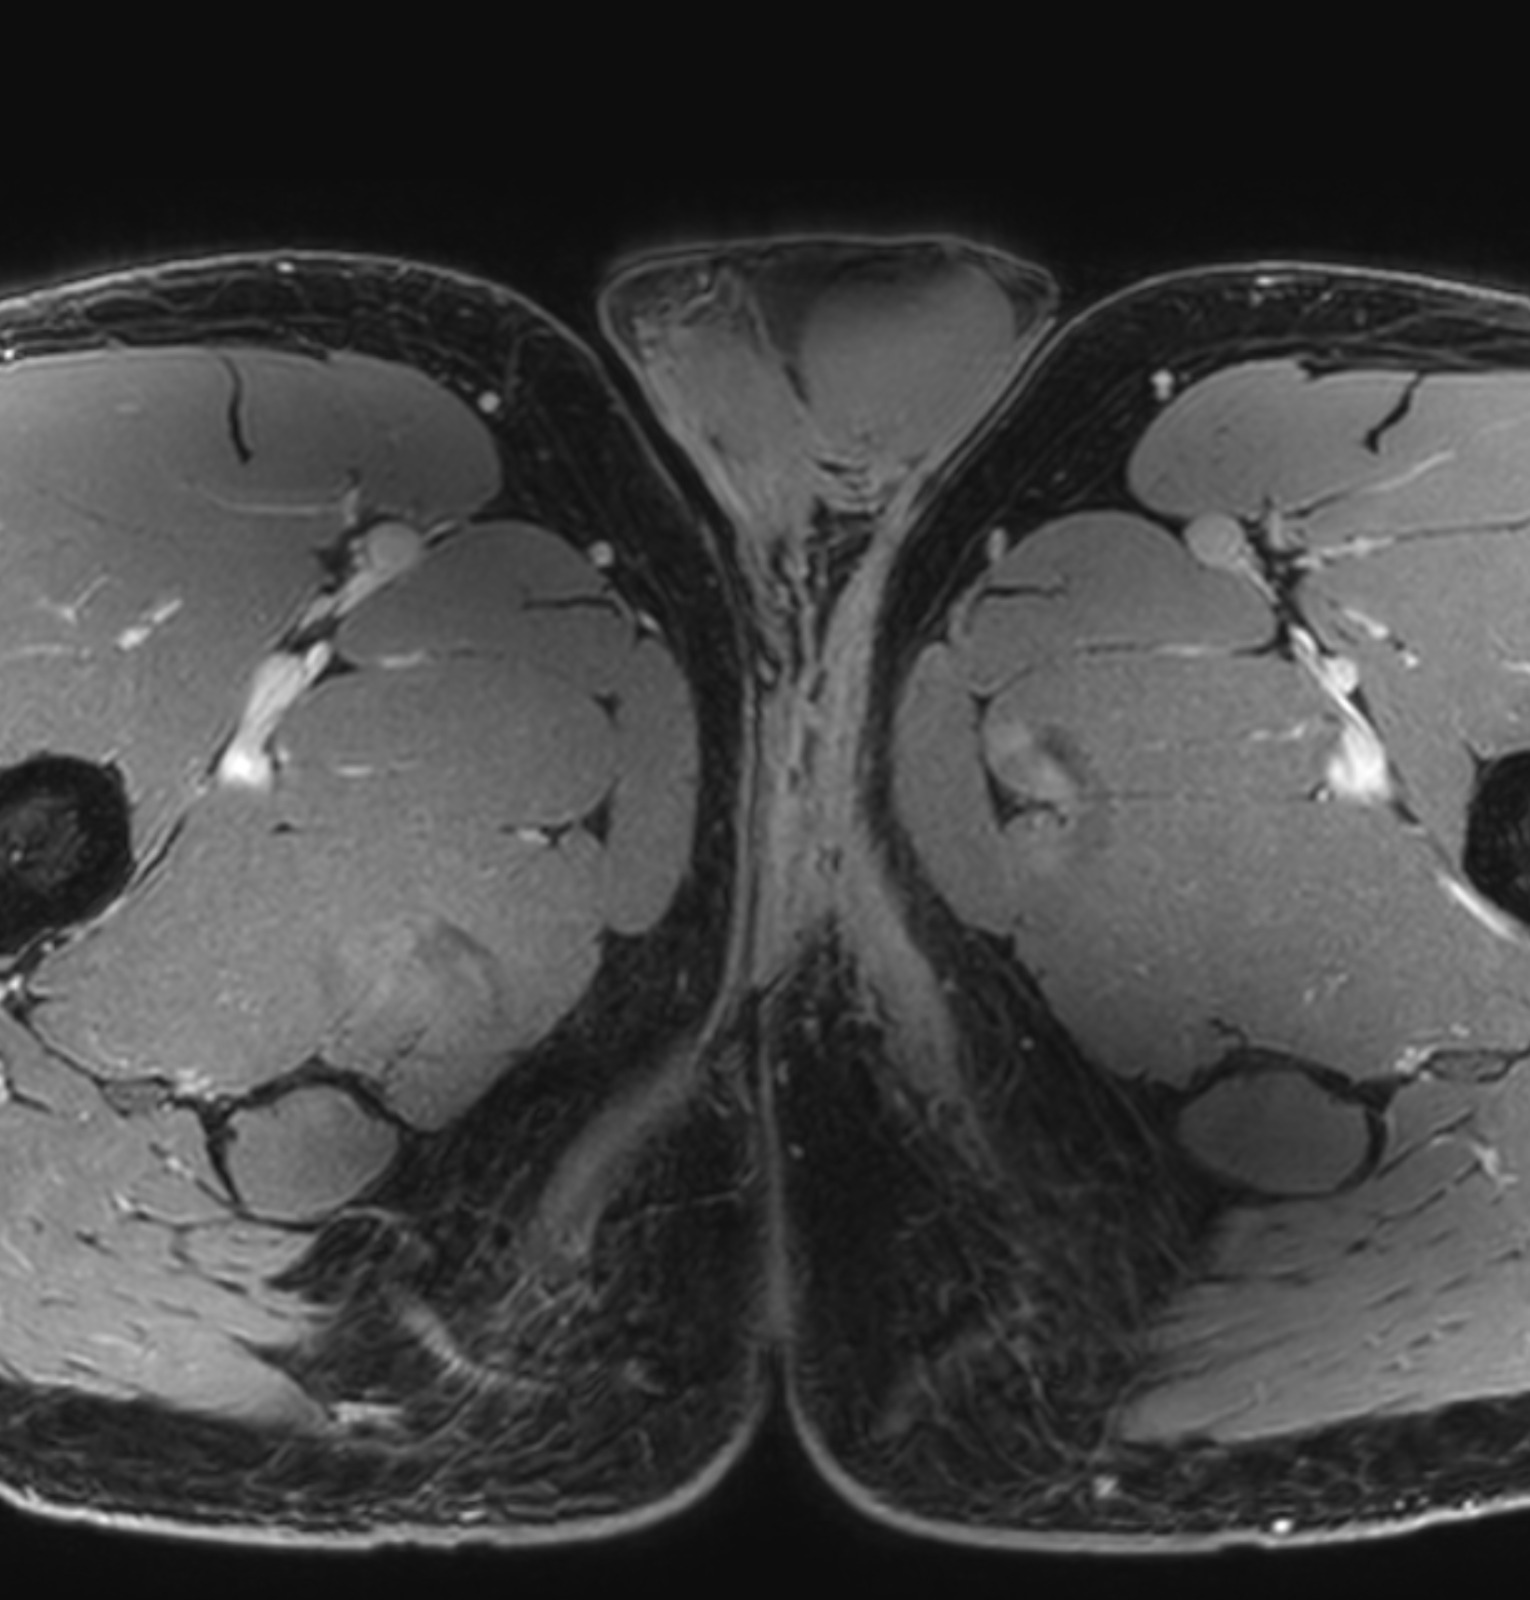

Hx: 37-year-old male, avid cyclist (125+ miles per weekend), experiencing perineal pain, clinical suspicion for soft tissue mass vs. hamstring tendinopathy.

MR Findings: Edema and scarring of the subcutaneous layer of bilateral perineal fat pads/medial proximal thighs, left greater than right, without significant contrast enhancement.

Diagnosis: "Biker’s Saddle Soreness" (also known as "Cyclist Perineal Pain", "Cyclist’s Nodule").